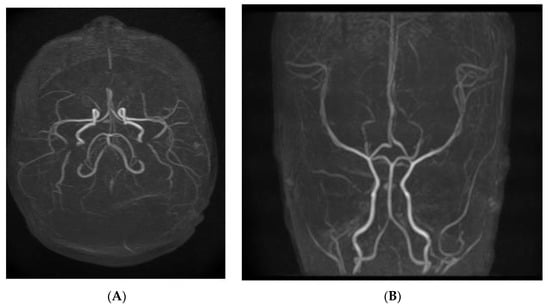

2. Case Report